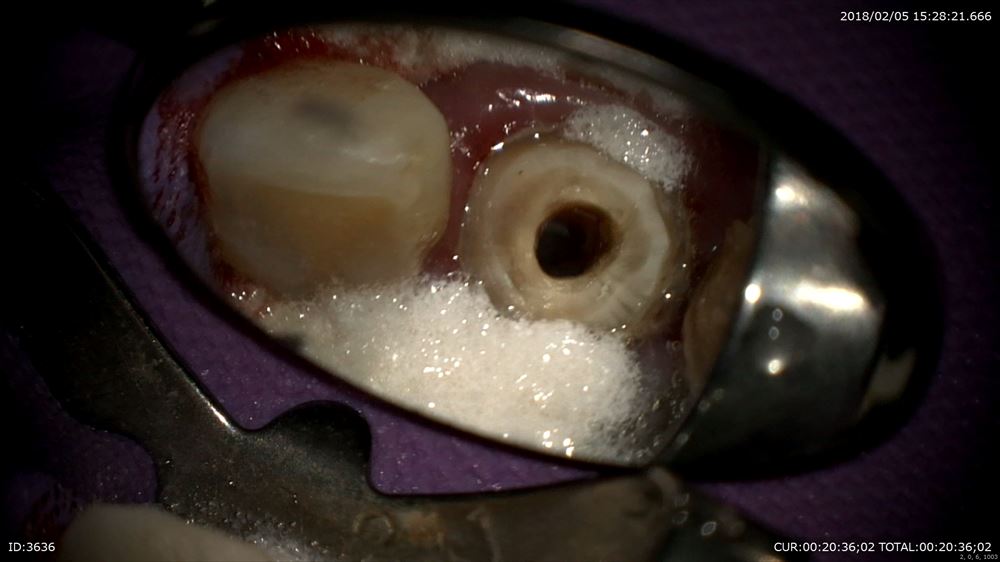

今日が2回目イスムスの整理や根管形成の終盤。

うん。感染をしっかり色で分けて確認

確実に。マイクロエキスカ

イスムスに感染これはマイクロスコープでしか見えません。

こんな状態から 右 ここまで2回 左 次回終了。